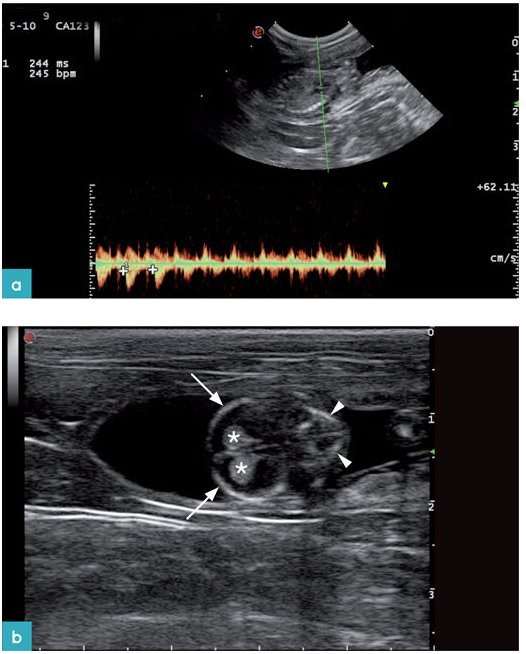

妊娠期第16天超声影像上可见胚胎,是在子宫腔的胎囊内的高回声结构。妊娠期的第16~18天可识别胎儿心脏、第16~20天可探知胎儿心率,第20天的心率为227土3次/每分钟(bpm)。此后胎儿心率逐渐下降,至妊娠期第40天时心率平均值变为2241次/每分钟,第60天心率降至223±7bpm。脐动脉和胎儿主动脉在妊娠20天是可见,颈总动脉和肾动脉分别在妊娠的第30天和第40天可见。

关于使用脉冲多普勒超声对整个妊娠期中子宫动脉和脐动脉阻力指数的变化的报道已有数篇,但不同报道的结果之间具有一定的矛盾性。总体来讲,阻力指数的变化一般会随着妊娠期的发展而降低。